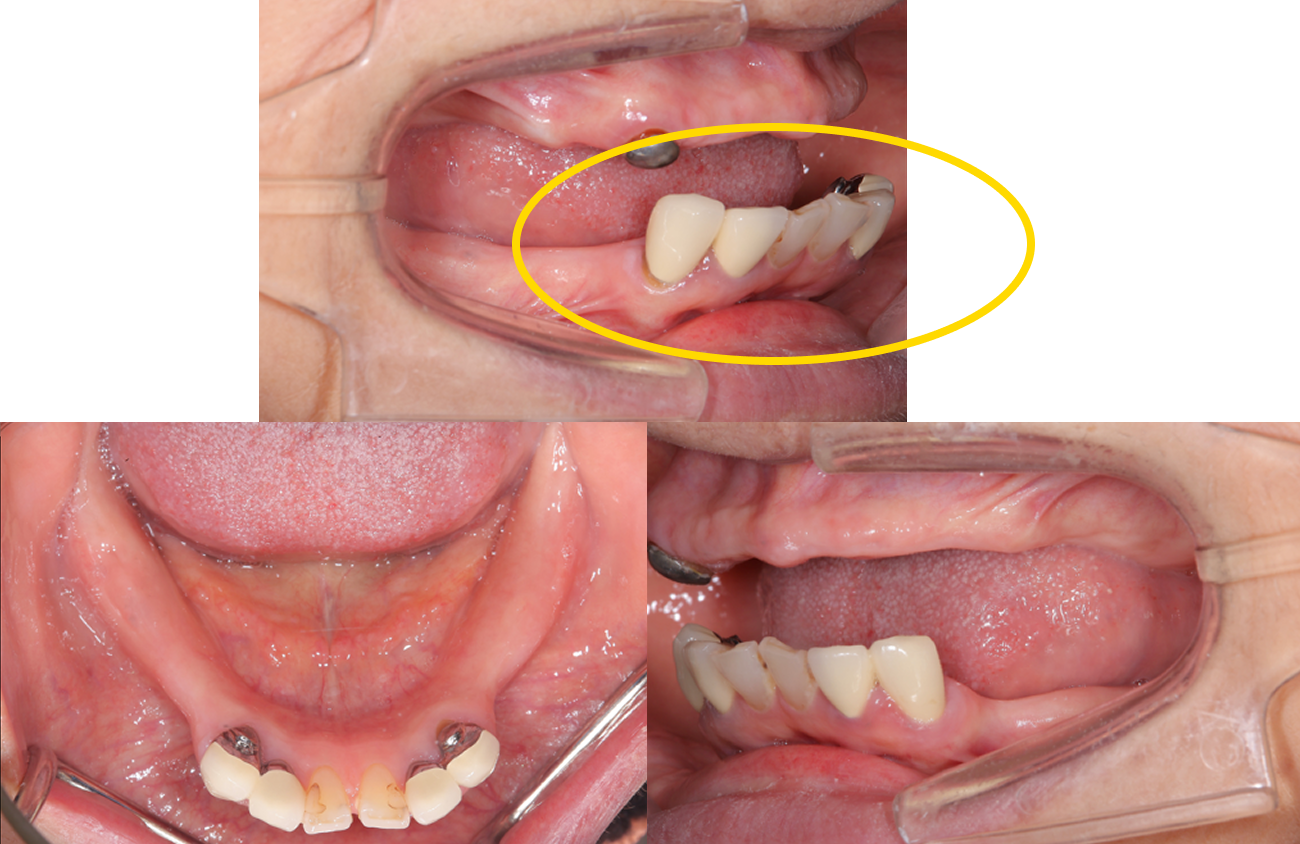

主訴:左下の歯が外れた。

治療概要:左下の歯が外れたことがきっかけで来院されました。右下と左上には歯がない状態でした。

外れた左下の歯ですが、歯茎から出ている歯の部分が明らかに短く、この状態で被せ直しをしても維持力がないためすぐに外れてしまう事が予想されました。

また、奥歯がないためこの歯には噛む時の力が過剰にかかってしまいます。

この方の場合右の歯も少なく、主訴である左下の歯だけ治療をしたとしても今残っている歯も含めてどんどん悪くなることが予想されました。

このような理由で口腔全体を含めた「全顎の治療」計画を提案させていただきました。

現状残っている歯の状態から、この患者さまは「生理的咬合」であると診断し、現状噛んでいる歯の位置の修正とは行わずに、歯がないところ、歯が欠けているところを治すだけで安定すると考え治療を行っています。

この歯(黄色の印)は顎を横に動かした時に強い力が加わり、歯の周囲の組織にダメージが出ているため、力をコントロールするために歯の形を修正が必要です。

右の奥歯についても歯が伸びてしまっているのでこちらは部分的な矯正治療と歯茎の手術で対応しています。